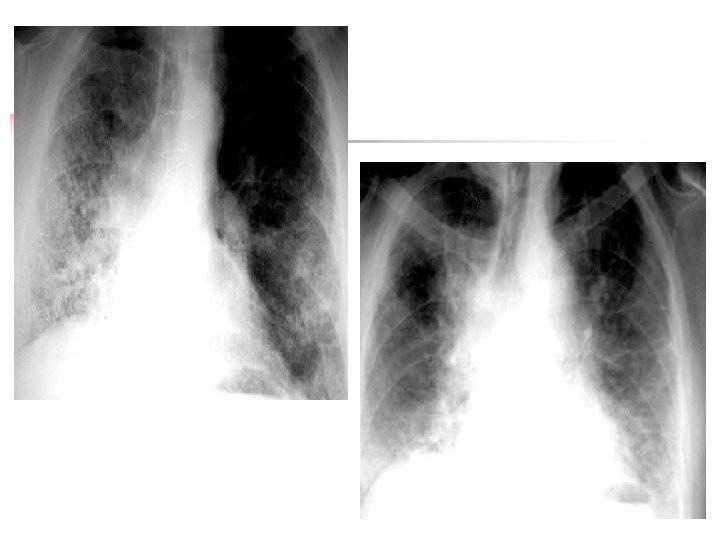

La fibrose pulmonaire idiopathique n n L'interrogatoire élimine un éventuel agent causal: inhalation d'aerocontaminants mineraux ou organique, prise de médicaments connu pour pouvoir donner une pneumopathie interstitielles. A l'examen clinique, il n'ya aucun signe de connectivite. Radiographie n n n Prédominance basale et périphérique Opacités réticulées ou réticulo-nodulaires Destruction en rayon de miel Hyperdensité en verre dépoli localisées Diminution du volume pulmonaire Effacement des contours du coeur et du diaphragme

Tomodensitométrie Lésions prédominantes en périphérie et en sous pleura+Régions inférieures et postérieures des poumons. n Rayon de miel n Réticulations fines intra- lobulaires n Verre dépoli (n'est jamais le signe dominant): n les hyperdensités en verre dépoli n épaississement pleuraux et sous pleuraux irréguliers n épaississements péribronchovasculaires irréguliers

Rayon de miel basal bilatéral, distorsion bronchopulmonaire : fibrose débutante